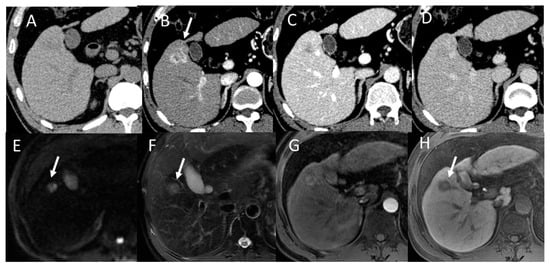

2.1. HCC Imaging on CT

2.2. HCC Imaging on MRI

3.6. Gadoxetic Acid Enhanced MRI (EOB-MRI)

4.2. Early Hepatocellular Carcinoma (Early-HCC)

4.3. Well-Differentiated Hepatocellular Carcinoma (Well-HCC)

4.4. Moderately Differentiated Hepatocellular Carcinoma (Moderately HCC)

4.5. Poorly Differentiated Hepatocellular Carcinoma (Poorly HCC)